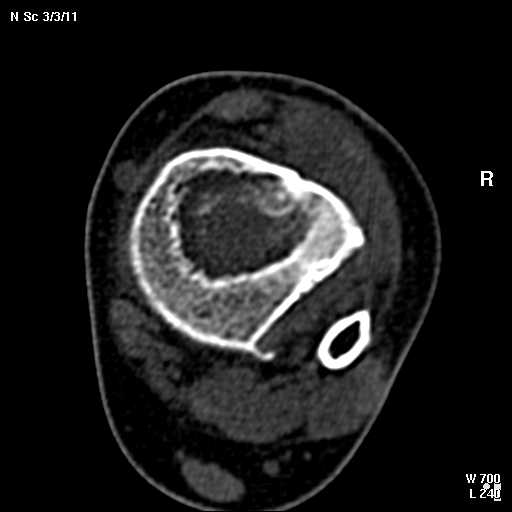

С подозрением на хондрому большеберцовой кости левой голени выполнена компьютерная томография. На серии томограмм получены изображения дистальных отделов левой голени. В дистальном метафизе на уровне нижней трети по латеральному краю определяется кортикальный очаг деструкции размерами 1,3x0,5x0,8 см. На уровне очага деструкции отмечается истончение кортикального слоя, без признаков его разрушения. Кость на уровне очага вздута. Структура окружающих мягких тканей не нарушена, объемных образований не определяется. Крупные нервные стволы и просветы крупных сосудов хорошо дифференцируются. Кожа и подкожно-жировая клетчатка не изменены.Заключение: КТ - признаки кортикального остеолитического очага деструкции в дистальном отделе метафиза левой большеберцовой кости без признаков разрушения кортикального слоя (остеогенная саркома?).19.11.2002 г. осмотрена онкологом, выставлен диагноз: саркома левой большеберцовой кости?Лабораторные исследования: - ОAK от 06.11.2002 г. - L - 11,3х109; эр. - 4,47хЮ12; НЬ - 117 гр./л; Ht - 33,6%; тр. -208x109; СОЭ - 38 мм./час, э-1; п-7; с-55; м-4; л-33.В отделении детской онкологии 11.12.02 выполнена операция: секвестр-некрэктомия н/3 левой большеберцовой кости.Послеоперационный период без осложнений.Проведено лечение. Линкомицин 150 мгхЗ р./д., обезболивание (анальгин, димедрол). Швы сняты 23.12.02, заживление первичным натяжением.Получен результат гистологического исследования: хронический остеомиелит. Данных за онкопроцесс нет.На приеме врача ортопеда поликлиники с жалобами на усиление болевого синдрома 03.01.03. Наложена задняя гипсовая лангета. Назначен противовоспалительная терапия, препараты Са и кальцийтониновые препараты. На фоне проводимого лечения болевой синдром купировался. На серии рентгенограмм (январь-февраль-март) На нижней трети левой большеберцовой кости наличие дополнительного кортикального очага диструкции с размерами 1.5x0,5 см., в динамике отмечается увеличение в размерах.С подозрением на рецидив хронического остеомиелита большеберцовой кости левой голени выполнена компьютерная томография.19/03/2003 На серии томограмм получены изображения дистальных отделов нижней трети левой голени и мягких тканей.В метафизе определяется очаг деструкции с четкими, неровными контурами, неоднородной структуры, за счет костных балок, размерами 1.8x1.8x2,4 см, плотностью 29 ед Н.В дистальном методиафизе. по латеральному краю, определяется кортикальный очаг деструкции, размерами 0,6x0,5x2,0 см, неоднородной структуры, за счет наличия фиброзных и костных балок, кортикальный слой истончен, без признаков разрушения.Структура окружающих мягких тканей не нарушена, объемных образований не определяется. Крупные нервные стволы и просветы крупных сосудов хорошо дифференцируются.Кожа и подкожно-жировая клетчатка не изменены.ЗАКЛЮЧЕНИЕ:КТ-картина состояния после операции. Формирование постоперационной, внутрикостной кисты. КТ-признаки объемного образования нижней трети левой большеберцовой кости, вероятнее всего фиброзная дисплазияРЕКОМЕНДАЦИИ: МРТ левого голеностопного сустава с захватом нижней трети голени.Лабораторные исследования: OAK от 05.03.2003 г. - L v 7.0х109; эр. - 4,74хЮ12; НЬ - 130 гр./л; Ht - 37%; тр. -274x109; СОЭ - 4 мм./час, э-1; п-1; с-53; м-3; л-42.Вопросы: уточнение диагноза? (хр.остеомиелит, обострение? Или все таки онкопроцесс) какие исследования провести? тактика лечения? КТ-снимки во вложении. Заранее благодарен!С уважением, Н.П.Козел.